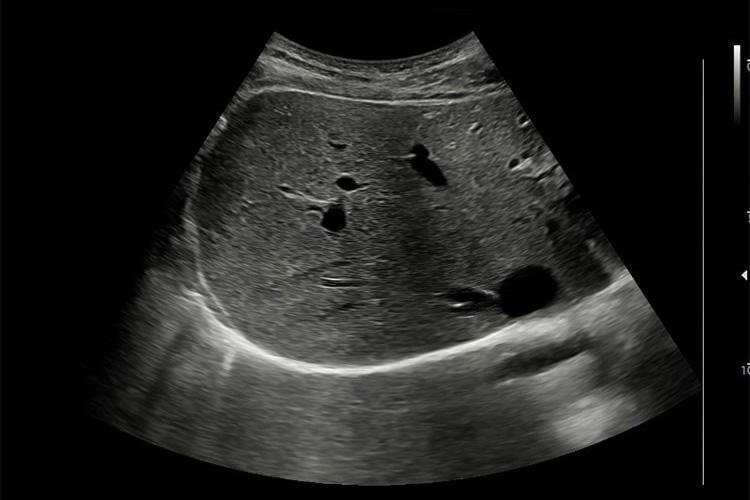

②腹部超音波検査

腹部超音波検査のイメージ

脂肪肝・脂肪肝炎を起こした肝臓は腫大します。また脂肪は超音波の反射源になるため白く見えます。そのため、正常の肝臓と比べると脂肪が沈着した脂肪肝は白っぽく輝いて見えます。そのほか肝腎コントラスト横隔膜や脈管の不明瞭化といった所見を確認します。

また超音波減衰を利用した測定法(Attenuation imaging)や、せん断波の伝播速度から組織の硬さを測定するShear Wave Elastographyも施行可能となっており、検査の幅が広がっています。